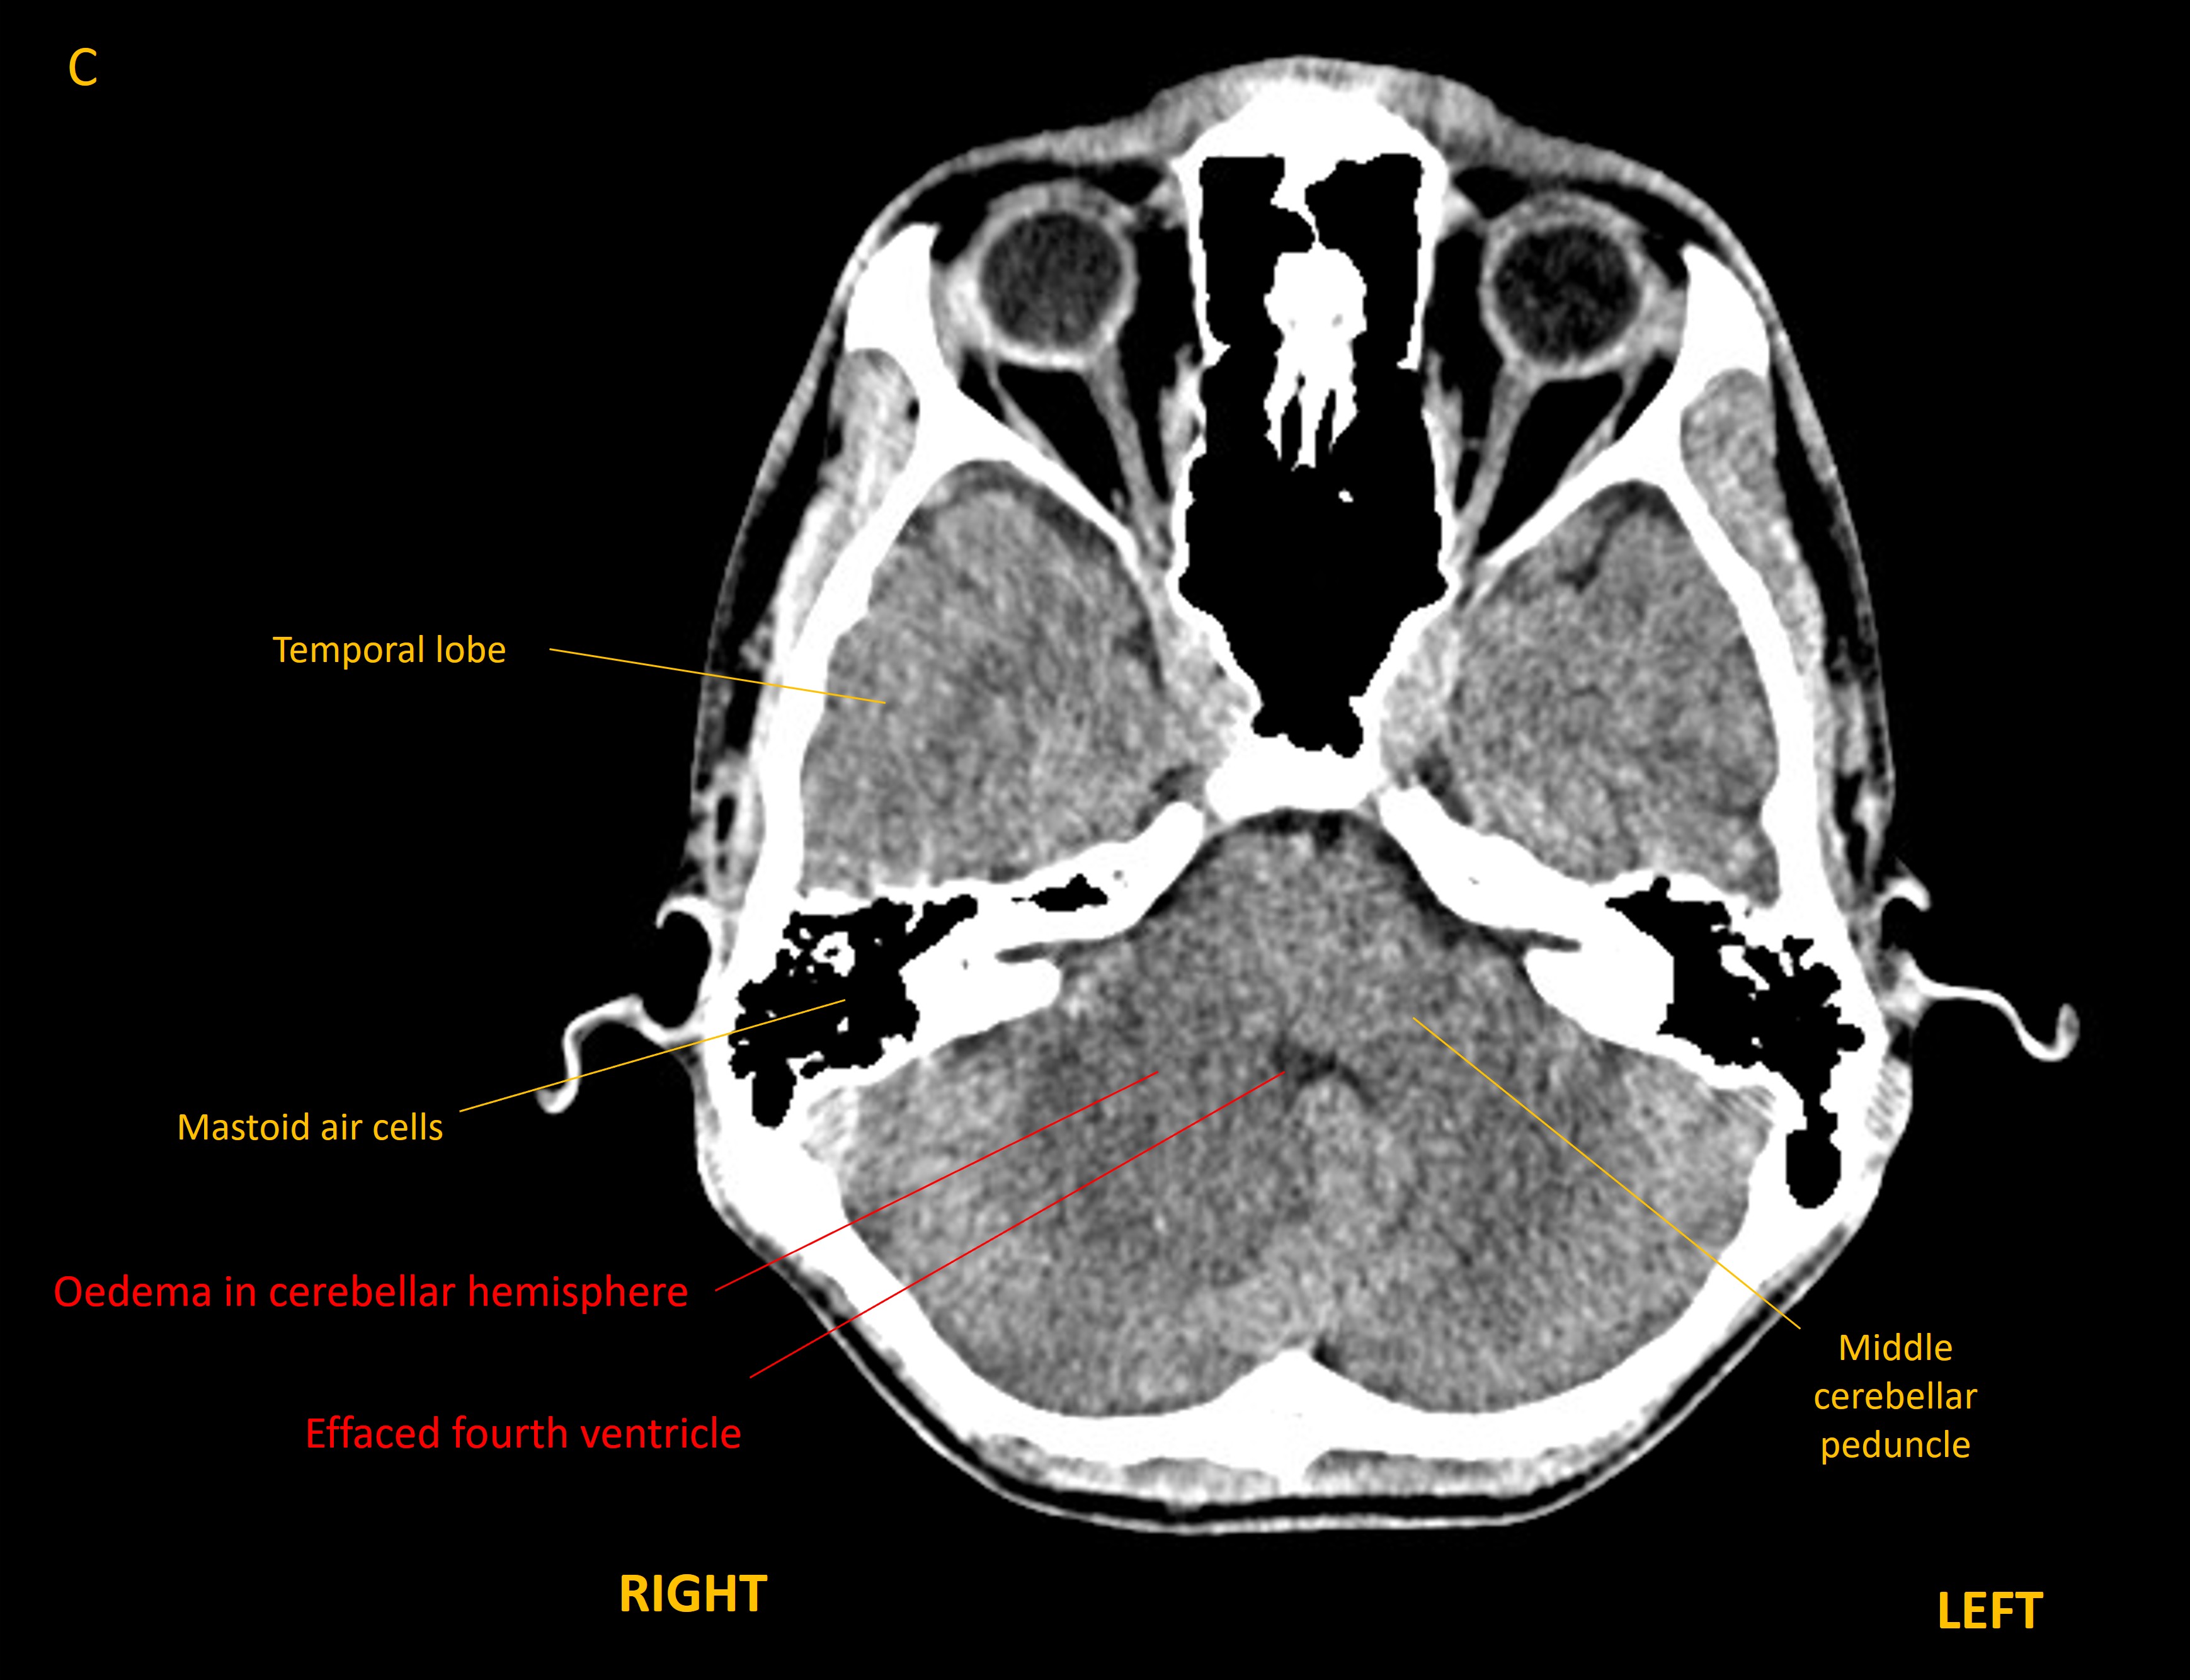

However, he deteriorated 5 weeks later, with headache, vomiting, vertigo, worsening ataxia (walking as if drunk), and dysarthric speech. CT imaging showed hydrocephalus developing - with dilatation of the temporal horns of the lateral ventricles - as well as effacement of the fourth ventricle lower down.

Axial CT brain